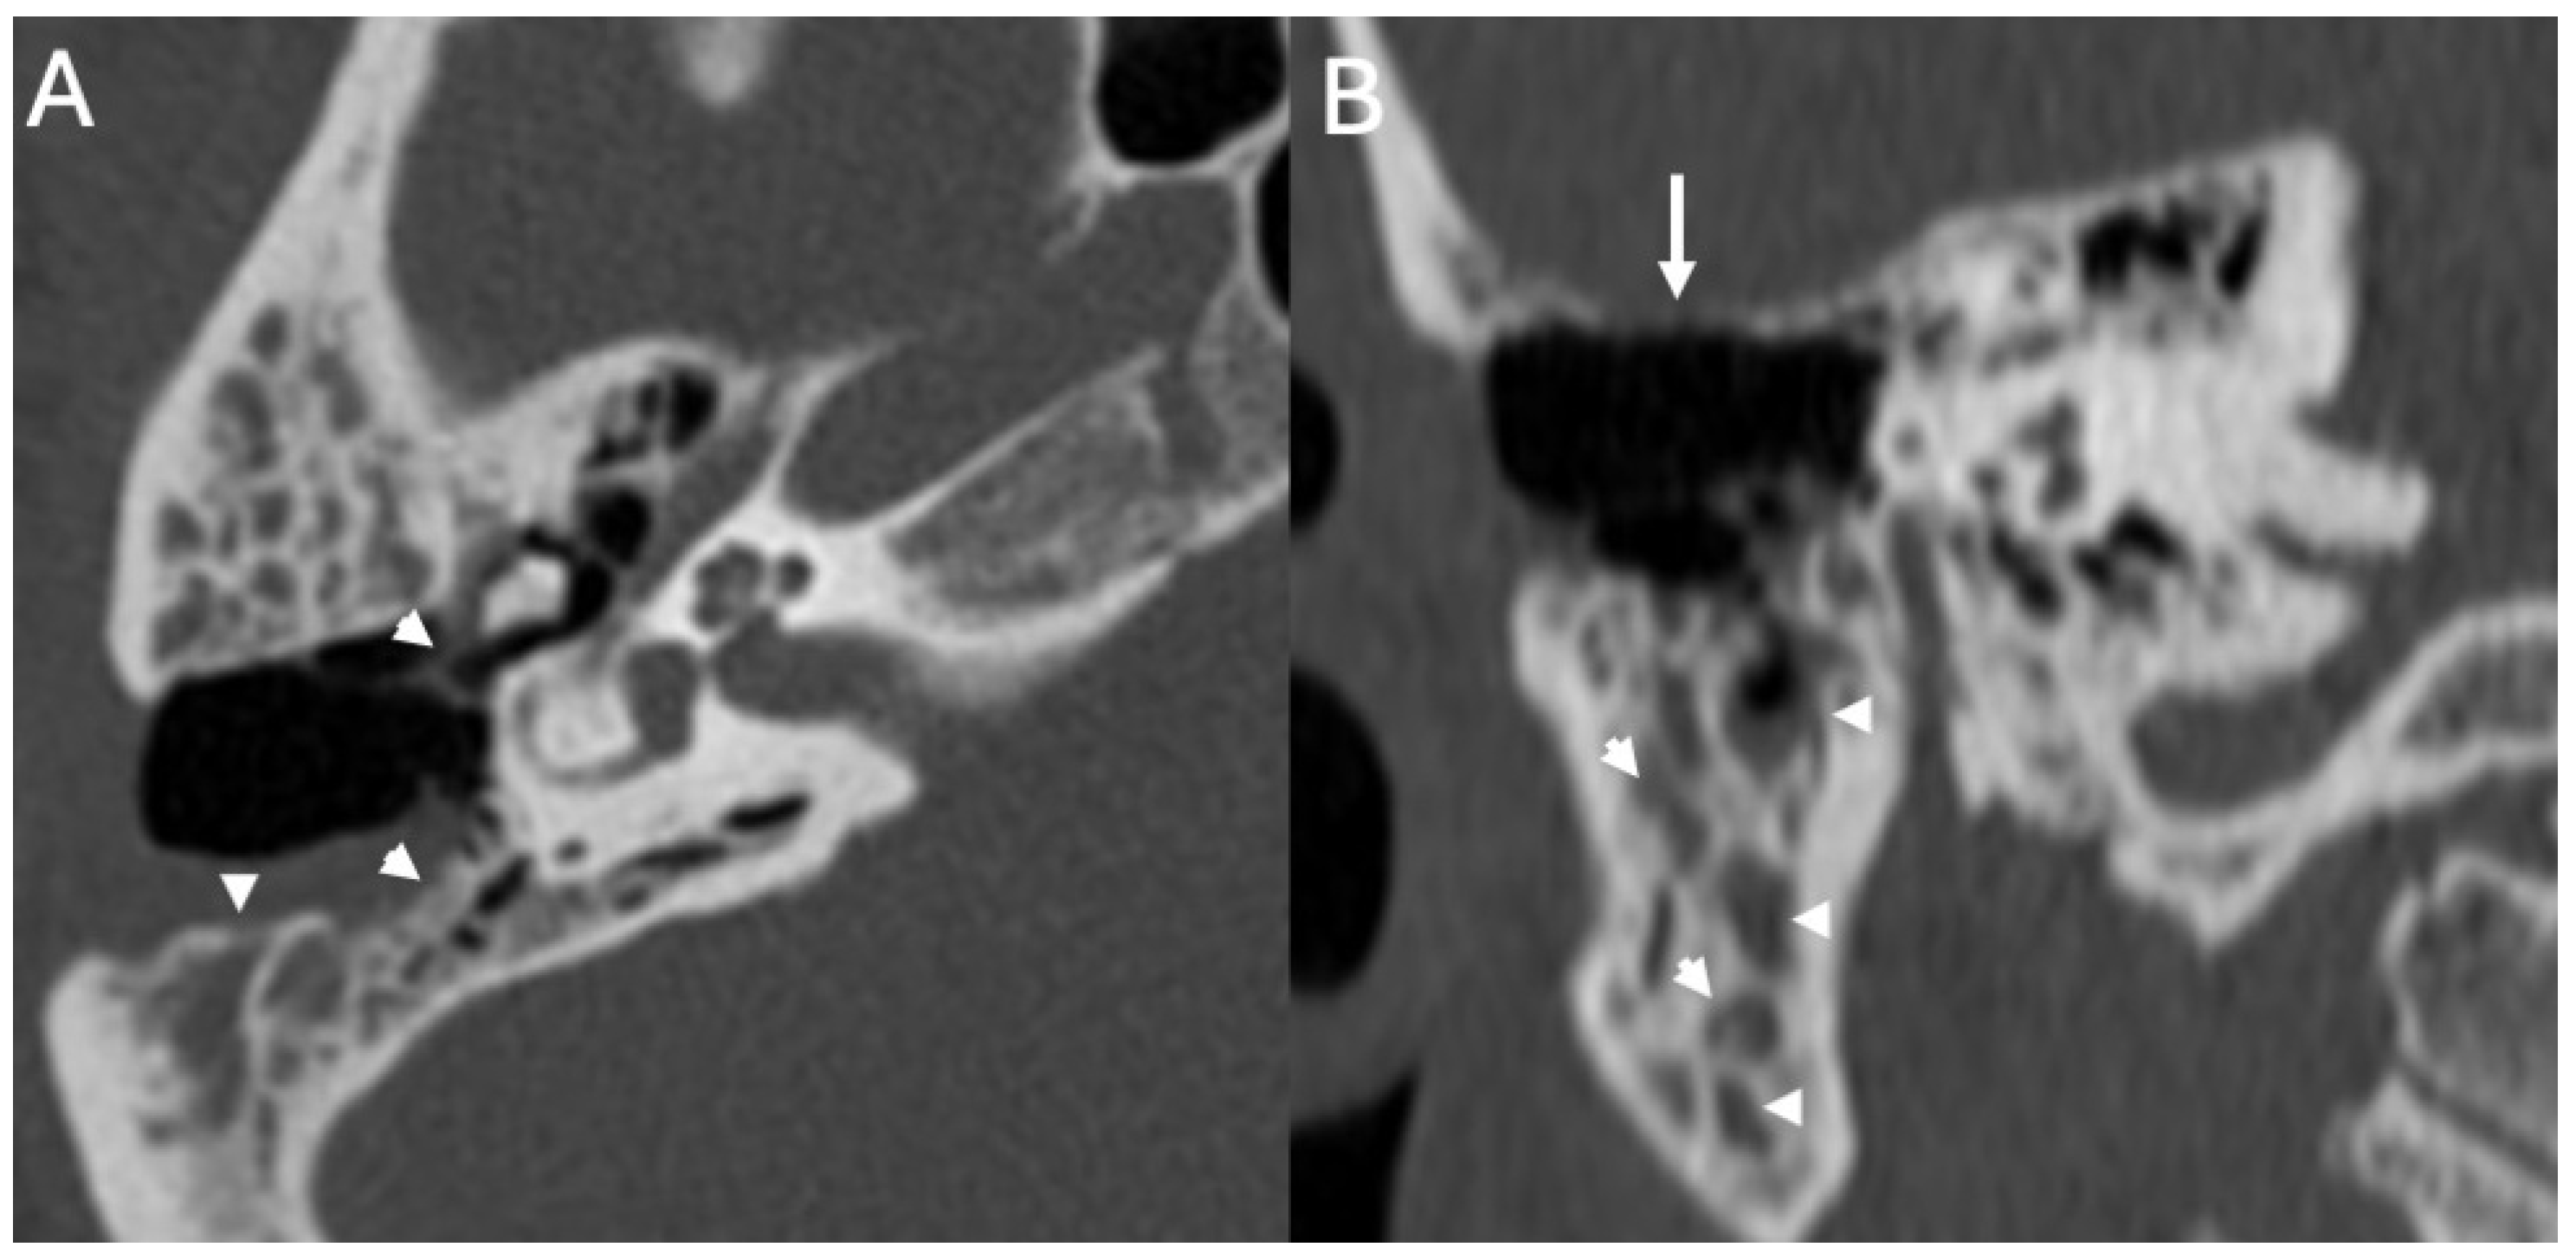

3.1. Otomastoiditis

3.1.1. Imaging

| Otomastoiditis and Otogenic Meningitis | Saat et al., 2015 [17]; Rubini et al., 2024 [18]; Vazquez et al., 2003 [19]; Bruschini et al., 2017 [20]; Barry et al., 2019 [21] | Retrospective studies, imaging reviews, and case reports | HRCT and MRI identify middle ear/mastoid infection and intracranial spread; meningitis occurs in up to 35–46% of untreated cases. |